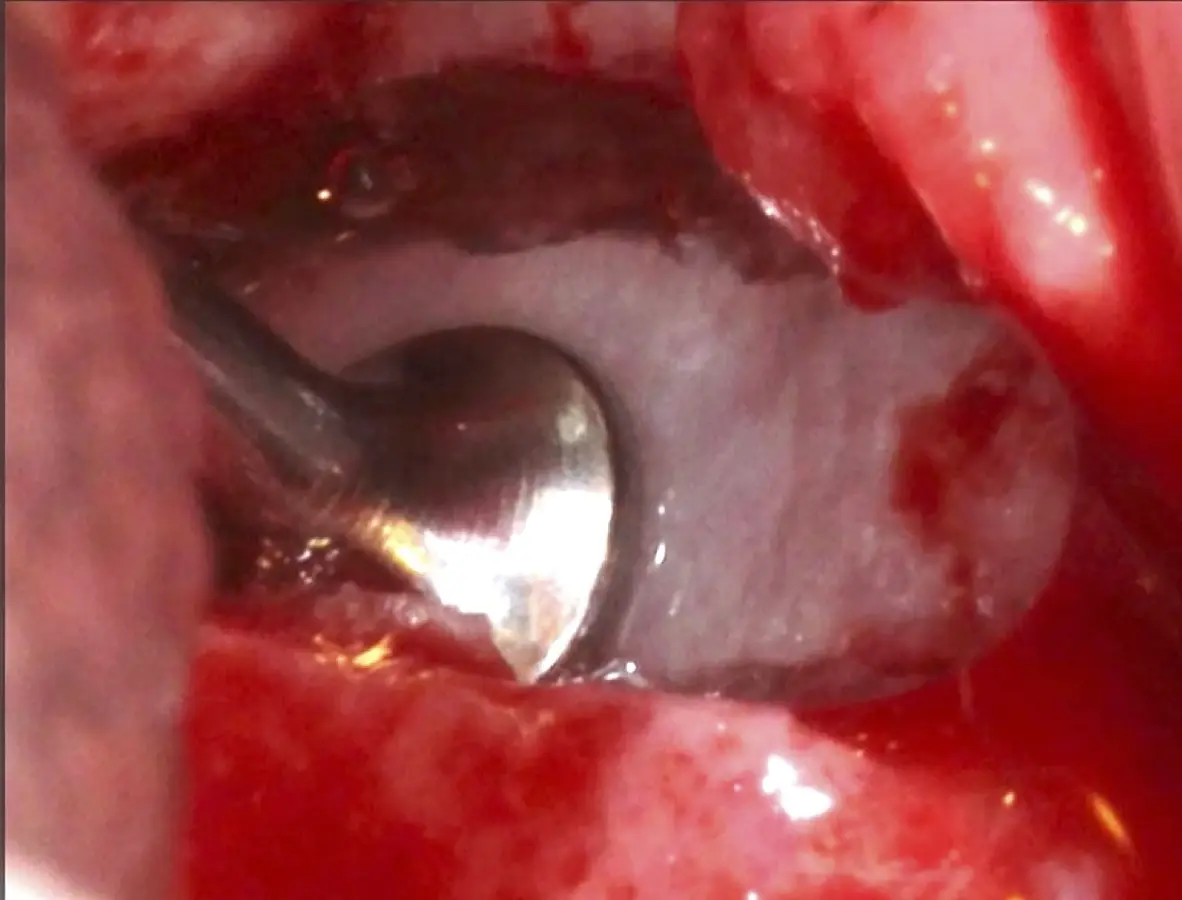

La técnica se inicia con la colocación de anestesia infiltrativa, posteriormente se realiza una incisión crestal o paracrestal con posibles liberantes verticales que deben de estar alejadas por lo menos 5 mm de los límites de la futura ventana y sobrepasar la línea mucogingival. Se realiza una elevación de colgajo, se inicia la antrostomía y antroplastía. Para ello, se emplea el inserto redondo diamantado de corte al momento de delimitar los bordes de la ventana de acceso. Luego se cambia al inserto aserrado liso de calibre fino con superficie diamantada, para profundizar y eliminar el hueso en el contorno de la ventana. Una vez que se traslucen los tejidos, se puede optar por el retiro de la tapa ósea o el levantamiento de ésta junto con la membrana.

Se inicia la elevación de la membrana de Schneider con el inserto redondeado no cortante en forma de disco, empleando movimientos suaves. El levantamiento puede complementarse con elevadores convencionales, siguiendo la dirección mesiodistal. La fase de desprendimiento inicia con el piso y sigue hacia la pared mesial para terminar, y de ser necesario, hacia la pared posterior. Existen diversos insertos con angulaciones y longitudes para mayor accesibilidad16 (Figura 1).

El clínico puede retirar la tabla ósea o introducirla como “tienda de campaña” dentro del seno maxilar. En cualquiera de las alternativas, es importante evaluar la presencia de tabiques óseos y de la arteria postero alveolar superior.